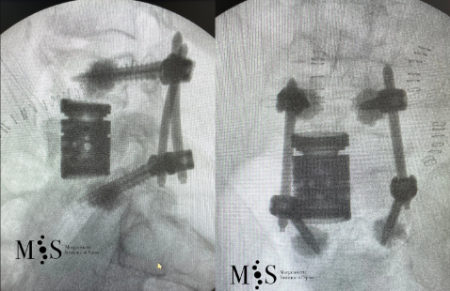

Estabilització percutània de fractures vertebrals inestables

En casos de fractures vertebrals complexes, inestables, comminutes, etc. es requereix una estabilització addicional de la fractura mitjançant una artròdesi percutània, i en alguns casos en els quals hi ha compromís neurològic, una descompressió del canal medul·lar. L’artrodesi percutània permet estabilitzar l’estructura compromesa de la columna vertebral i descarregar la càrrega del pacient sobre la fractura. Addicionalment se solen cementar les vertebres artròdesis i la fractura vertebral mitjançant cifoplastia.

Fractura Vertebral Ejemplo de Caso Clínico

Cas clínic d'una resecció (corpectomia) i reconstrucció vertebral lumbar en una fractura esclat de nivell L4.